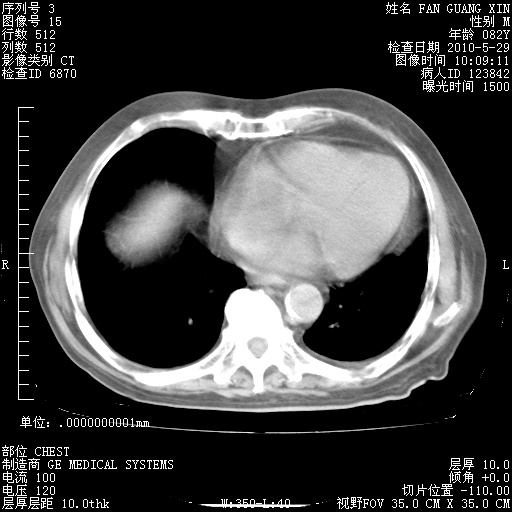

再治疗10天后的肺部CT 纵膈窗